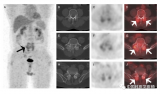

胡玉敬:上皮样血管内皮瘤的18F-FDG PET和骨显像

本例患者主要症状为左足局部慢性疼痛。常规影像学检查可见多发侵袭性的溶骨病灶,骨显像和18F-FDG PET显像均显示病灶呈高摄取,且局限于左下肢远端,最终经手术活检证实为上皮样血管内皮瘤,并进行局部肢体热灌注化学治疗。 2022-06-19 核医学PET/CT